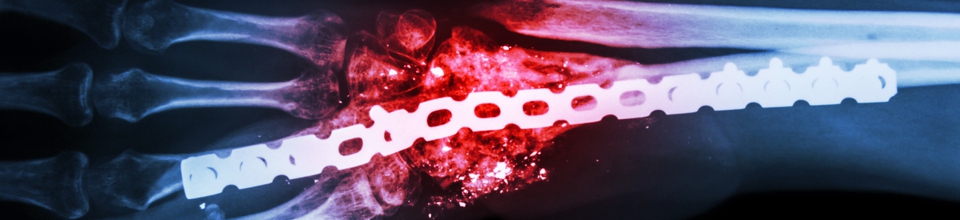

„Bis zu 1,2 Millionen Krankenhausinfektionen jährlich in Deutschland sind nicht schicksalhaft“

Wir vertreten deutschlandweit – ausschließlich - Patienten, die sich im Rahmen eines

Krankenhausaufenthaltes eine Infektion mit Keimen resistenter oder nicht resistenter

Art zugezogen haben oder Opfer einer verspätet diagnostizierten oder fehlerhaft behandelten

Sepsis geworden sind.